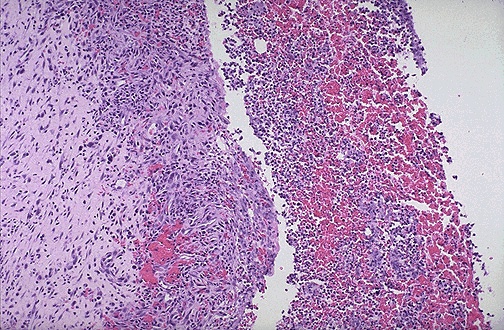

The wall of an abscess that is organizing has

granulation tissue

, seen here at the left. The

purulent exudate

with some hemorrhage is seen at the right in the abscess center.